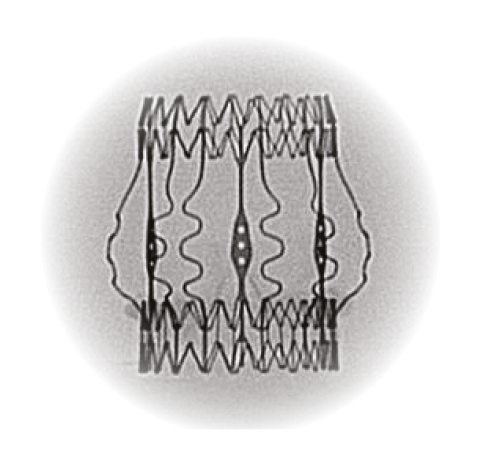

Superlastic stent

- Self-expands in place (no need to knot the sutures), ensuring optimal valve sealing.2

- Reduces the stress transferred to the leaflets.4

- CarbofilmTM coated to reduce inflammatory reaction and favor a gentle endothelialization.5,6,7

Perceval Plus boasts a distinctive design built around a superelastic stent that self-expands in place (no need to knot the sutures), ensuring optimal valve sealing.2

The Nitinol stent allows Perceval Plus to follow the physiological movement of the aortic root during the cardiac cycle, mimicking the native valve.10,11

Clear visibility

The Nitinol stent provides clear visibility under fluoroscopy and CT scan to identify landmarks which facilitate the ViV procedure.